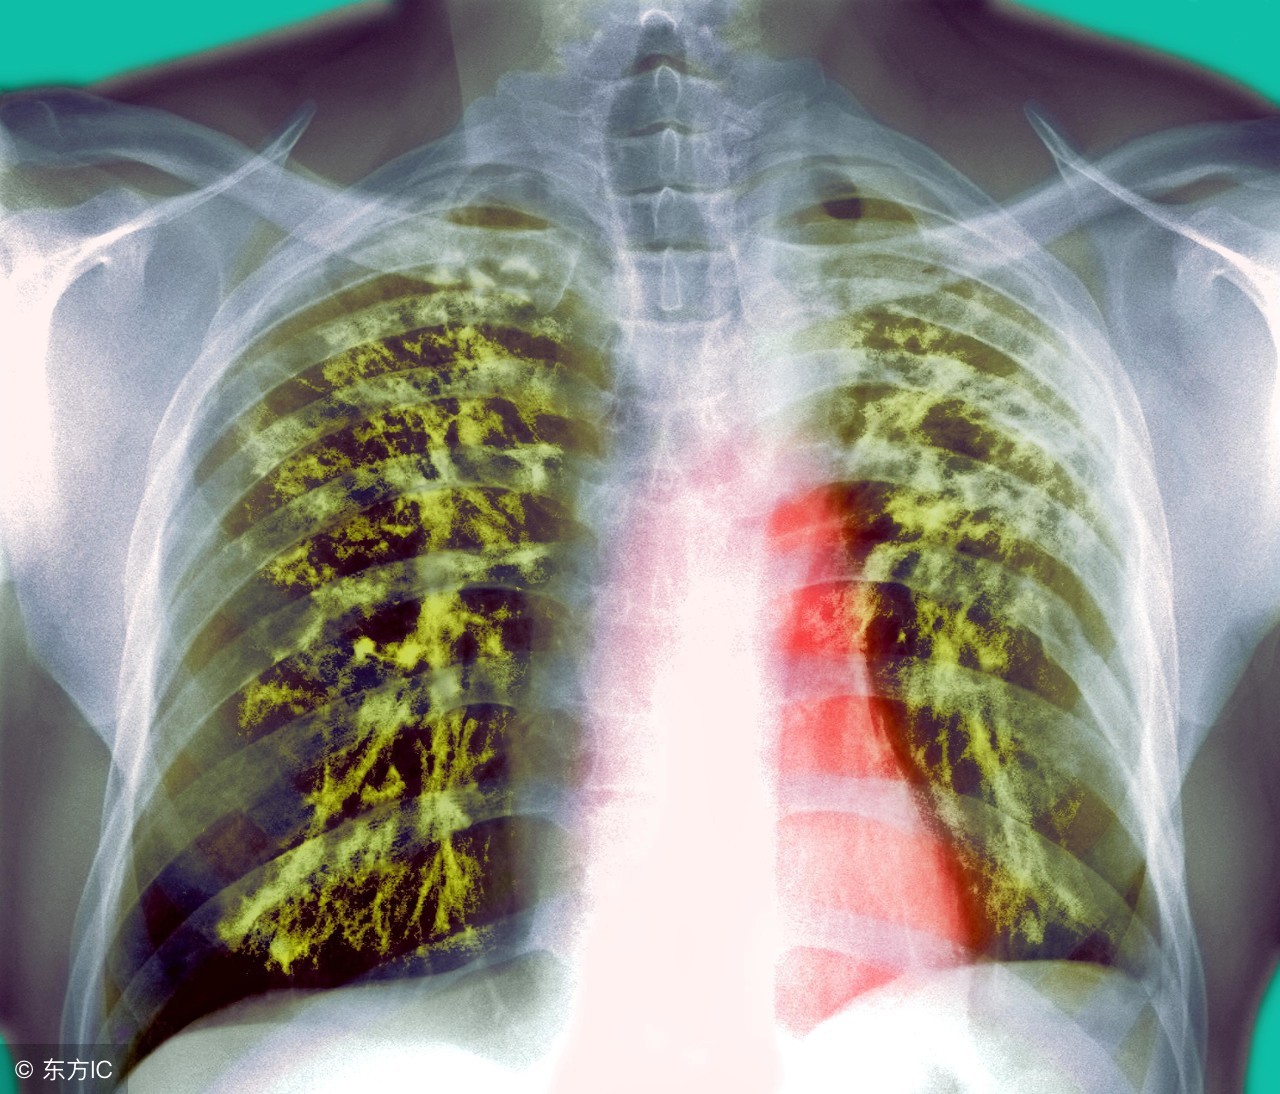

肺结核大家应该都听说过,但是肺结核吃什么依旧是一个疑问。大家都知道肺结核是由于病菌引起的疾病,治疗所花费的时间较为长,那么就需要配和日常的饮食啦。那么肺结核患者应该吃什么呢?下面告诉你,肺结核患者的饮食宜忌。